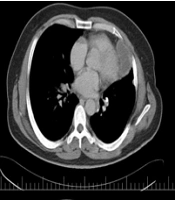

The Massive Asymptomatic Myo-pericardium Hydatid Cyst: A Rare Case Report

Mahmood Hosseinzadeh MalekiORCID,

Ghazaleh KhademianORCID,

Saeideh Imani MoghaddamORCID,

Fatemeh RamezaniORCID,

Mohammad Sadegh Sheikhi,

Mohsen YaghubiORCID*